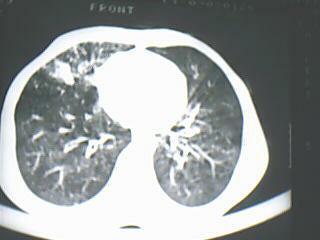

以下是引用随光逐影在2009-8-7 15:40:00的发言:[br]考虑右肺继发性肺结核并右肺上叶空洞形成,两肺支气管播散;不排除右肺上叶空洞内霉菌感染可能。

以下是引用jiangjing在2009-8-7 14:38:00的发言:[br]右上肺张力空洞,酐珞坏死灶,支气管扩张,多发播散灶,纵膈淋巴结显示,胸膜增厚---结核